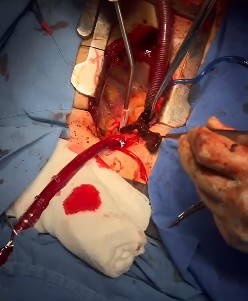

Ingresó a la unidad hermodinámicamente estable, taquicárdico, neurológicamente íntegro, con apoyo de oxígeno por puntas nasales. Tras ser valorado por el servicio de hemodinamia, se determinó que no era candidato a trombectomía mecánica por intervencionismo debido a que presentaba estabilidad hemodinámica y por encontrarse en ventana para fibrinólisis; sin embargo, durante la evolución hospitalaria presentó inestabilidad hemodinámica con presión arterial sistólica (PAS) <90 mmHg, por lo que se clasificó como PESI IV (riesgo de muerte alto). Se acepta por cirugía de tórax para trombectomía mecánica, e ingresó al quirófano, donde se encontró un trombo en las ramas principales y confluencia (Figura 3), el cual se extrajo sin eventualidades (Figura 4). Finalmente, ingresó a la unidad de cuidados intensivos para cuidados posquirúrgicos, con evolución favorable y posterior egreso sin eventualidades.

Figura 3 Trombectomía de grandes vasos. Presencia de trombo en vasos principales.